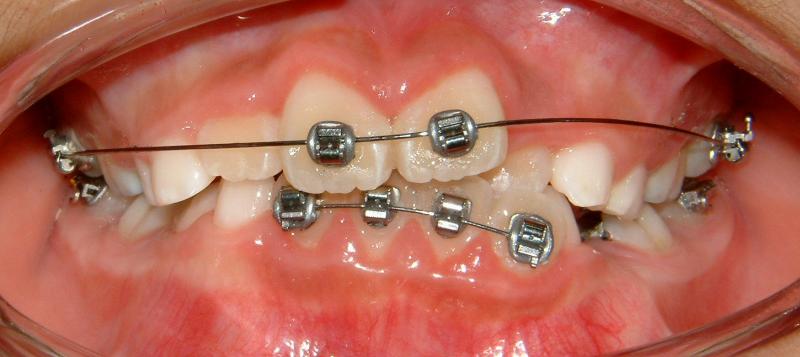

Case 1: 9 yr-old female

Fig. 1 View showing the initial